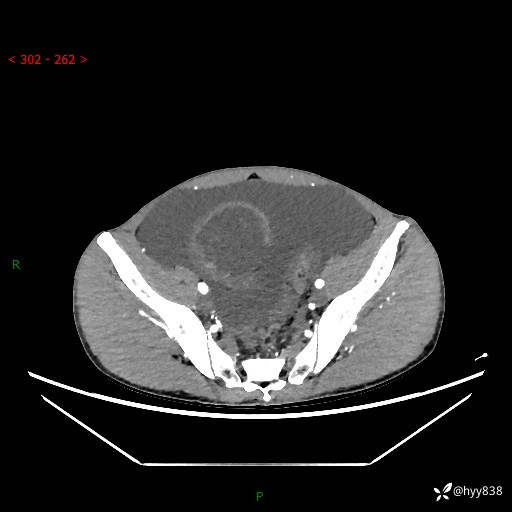

现病史:患者10天前无明显诱因出现腹部胀痛不适,无畏寒发热,无胸痛胸闷,无心慌气短,无恶心呕吐,无腹泻及黑便,无粘液血便及里急后重等症状,4天前在当地县人民医院就诊,行腹部CT示:下腹部占位性病变,腹腔及盆腔积液;今患者为求进一步诊治来我院治疗,门诊以“腹水”收治入院。 发病以来,精神饮食可,大小便正常,体重体力无明显变化。

腹部CT平扫+增强